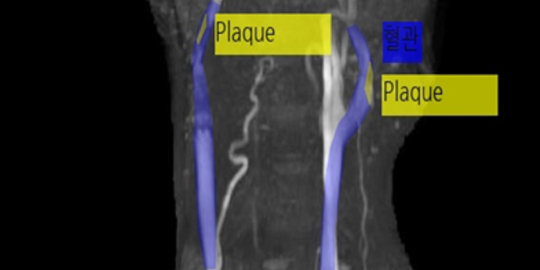

- 어노테이션 시각화 예시